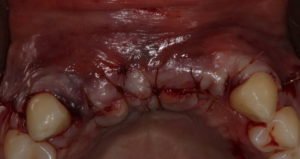

Paciente procurou a área de CBMF da Unicamp com a pré-maxila edêntula (Figuras 1 e 2) e foi submetido à técnica Screw Tent Poleutilizando os parafusos da linha Orth – Implacil de Bortolli (Figura 3). Do lado esquerdo da pré-maxila foram instalados três parafusos que apresentavam roscas em toda superfície, enquanto que do lado direito foram instalados três parafusos que não apresentam roscas no terço cervical (Figuras 4 e 5). Biomaterial associado com PRF (Stick Bone) foi adequadamente acomodado na região entre os parafusos e recoberto por membranas de PRF (Figuras 6 e 7). Uma sutura livre de tensão foi realizada para finalizar o procedimento cirúrgico (Figura 8).

figuras 4 e 5